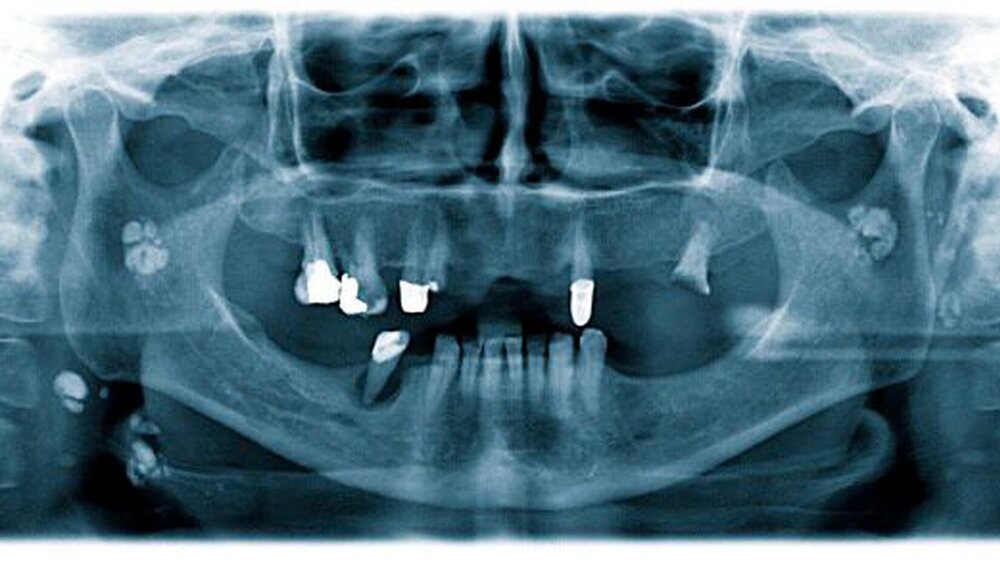

Eine 49-jährige Patientin stellte sich in der Schmerzambulanz zur weiteren Therapie vor. Aufgrund einer submukösen Abszedierung in regio 045 und eines Wurzelrestes in regio 027 wurde ein Orthopantomogramm zur weiteren Diagnostik angefertigt (Abbildung 1).

Dabei imponierten neben der periradikulären Aufhellung in regio 045 mehrere unregelmäßig angeordnete, wolkige, begrenzte Strukturen im Bereich des rechten und linken aufsteigenden Unterkieferastes. Außerdem waren unterhalb des rechten Ramus mandibulae in Höhe des Os hyoideum und im Bereich des linken Ligamentum stylomastoideum röntgenopake Strukturen sichtbar. Anamnestisch berichtete die Patientin von einer abgelaufenen Tuberkulose der Speicheldrüsen im Kindesalter, deren Spätfolgen im Sinne von Kalzifizierungen anhand der radiologischen Befunde palpiert werden konnten.